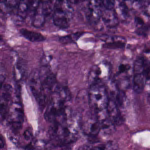

The idea of building a filter is to train a SVM to classify histopathologic images (HI) as relevant or irrelevant as illustrated in Fig. 1. For such an aim, we use the CRC dataset which is composed of images of 150150 pixels labeled according to the structure they contain. Eight types of structures are labeled: Tumor (T), Stroma (S), Complex Stroma (CS), Immune or lymphoid cells (L), Debris (D), Mucosa (M), Adipose (AD), and Background or Empty (E). The total number of images is 625 per structure/tissue type, resulting in 5,000 images. Fig. 2 depicts examples of the images from the dataset.

| (a) Adipose | (b) Complex Stroma | (c) Debris | (d) Empty |

| (e) Lympho | (f) Mucosa | (g) Stroma | (h) Tumor |